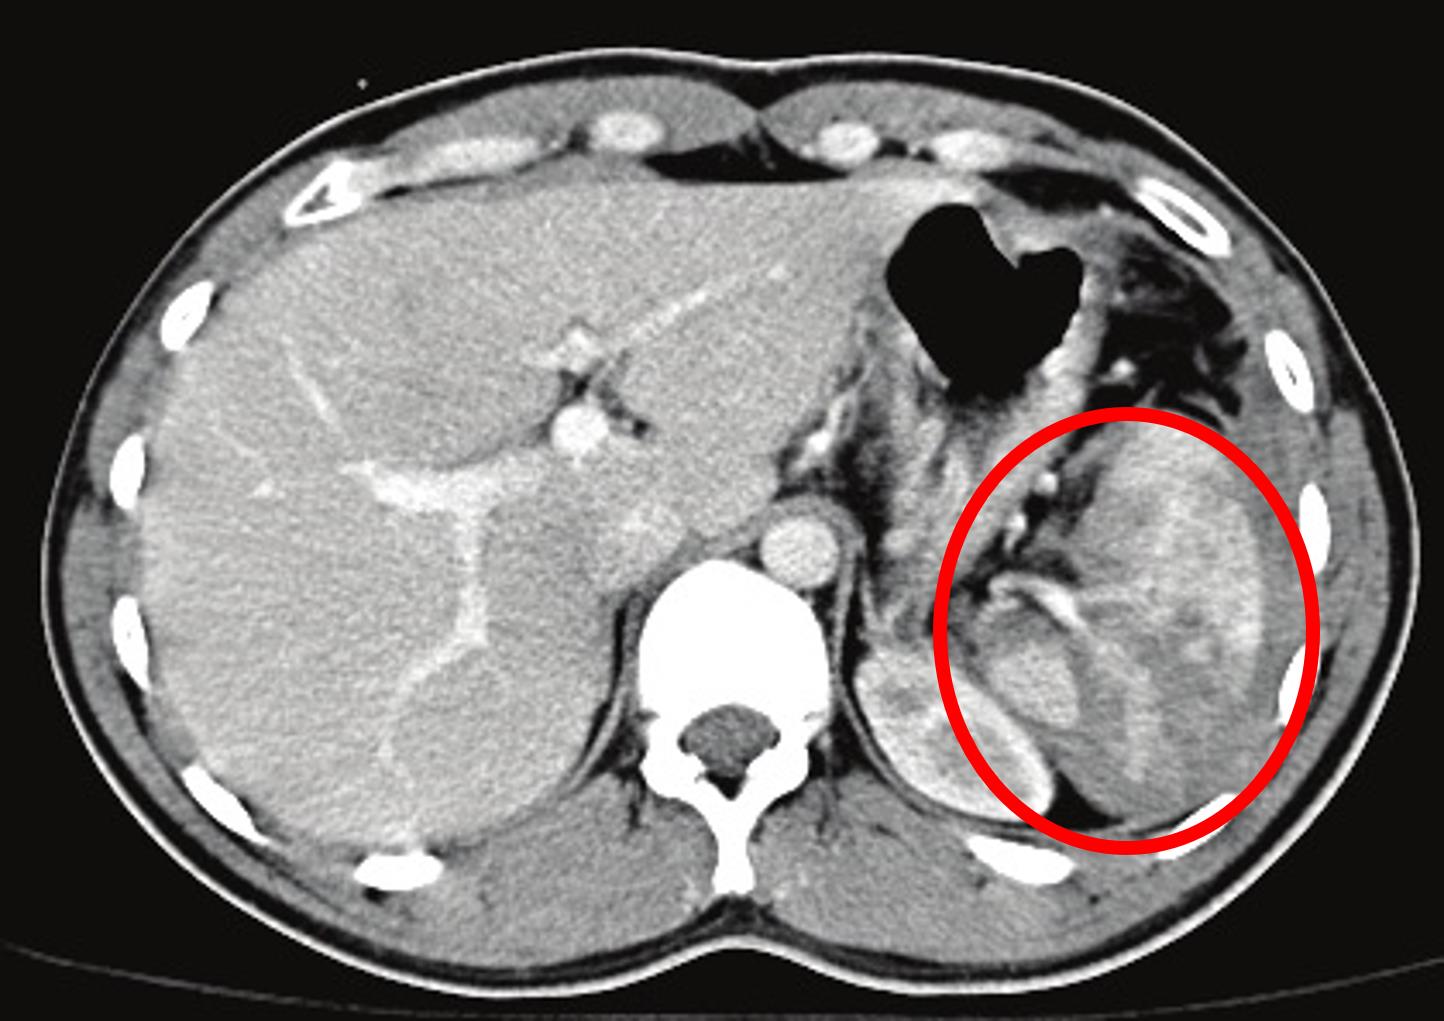

A 31-year-old skier is airlifted to the hospital after being involved in a collision with a tree. On arrival, she has severe pain in her abdomen and right leg. She has no significant medical history, is up to date on all vaccinations, and her last tetanus shot was 3 years ago. Her temperature is 36.7°C (98°F), blood pressure is 82/63 mmHg, pulse is 120/min, respirations are 20/min, and oxygen saturation is 97% on 2L oxygen nasal cannula. On physical exam, there are extensive ecchymoses and abrasions along her left posterior ribs and left flank. A radiograph of the right leg shows a midshaft tibial fracture. A CT scan of the abdomen is shown in Figure A. After the appropriate surgical intervention is performed for these injuries, which of the following would be indicated for post-operative care?

This patient with evidence of splenic rupture and hemoperitoneum on CT imaging most likely underwent emergency splenectomy. Subsequently, this asplenic patient will require vaccination against encapsulated bacteria such as S. pneumoniae, N. meningitidis, and H. influenzae.

Figure/Illustration A is an abdominal CT that demonstrates a traumatic appearance of the spleen with a perisplenic hemoperitoneum (red circle). These findings are consistent with a high grade splenic laceration.